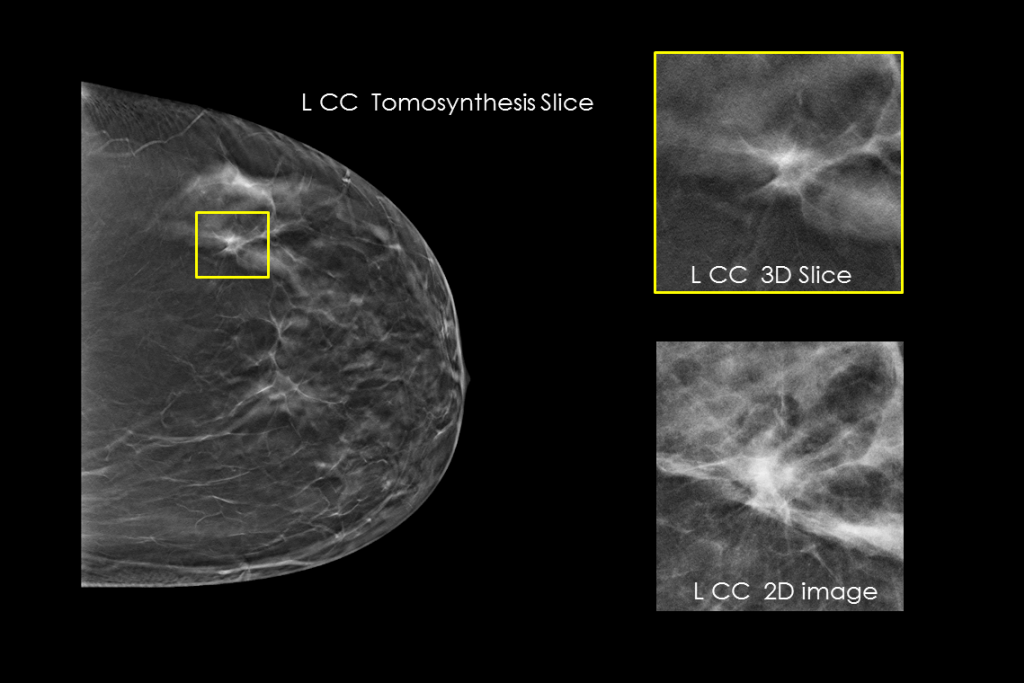

Immagini cliniche di una mammografia

Immagini cliniche di una mammografia con lesione sospetta

Immagini cliniche di una mammografia con tessuto mammario denso